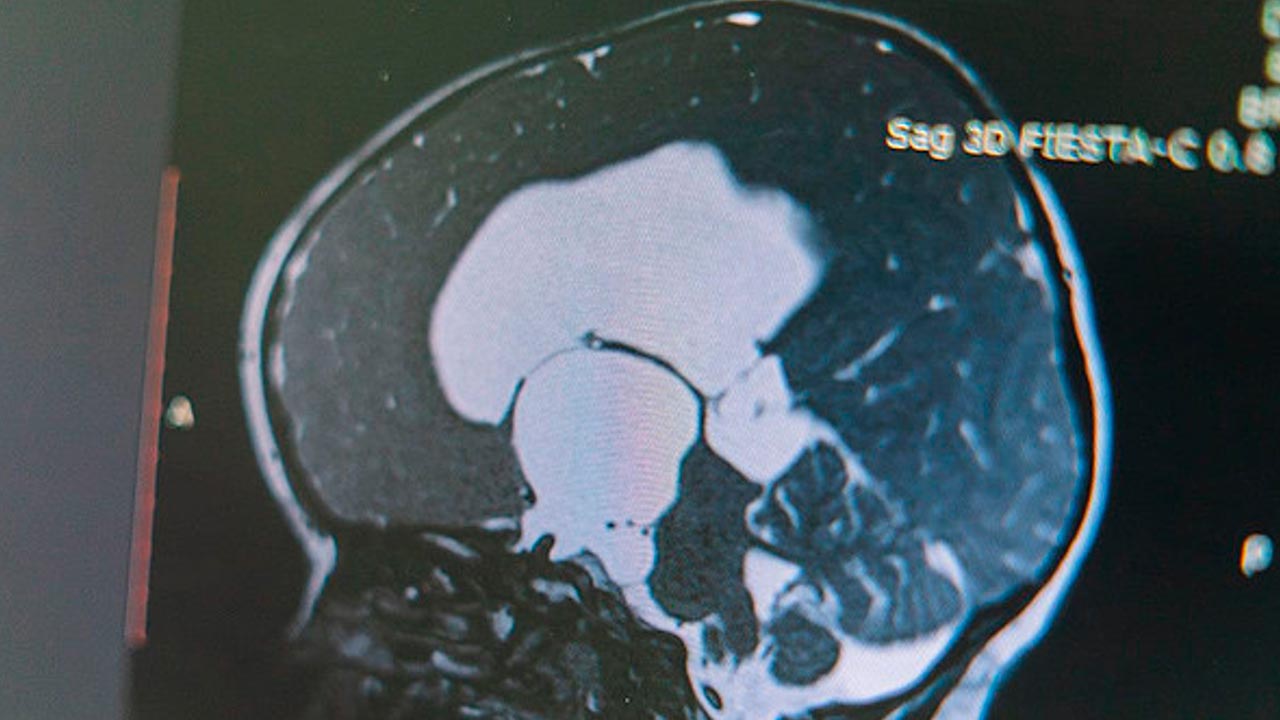

Но есть и ещё один "неуправляемый" фактор развития болезней мозга – наследственность. У Виктории Бузаевой именно по этой причине в мозге развилась опухоль. Если не лечить – возможен летальный исход. Удаление традиционными способами может привести к частичному параличу и инвалидности. В итоге команда областной клинической больницы решилась на уникальный для нашей области вариант: впервые медики "разбудили" пациентку во время операции, чтобы контролировать правильность работы отделов мозга.

Заведующий нейрохирургическим отделением РСЦ Иван Гладков комментирует: "Наш мозг не имеет болевых рецепторов, и пациент не чувствует дискомфорта. Он активно общается, выполняет команды".

Нейрохирурги, анестезиологи, специалисты УЗИ и функциональной диагностики трудились больше 4 часов. Их работа увенчалась успехом, Викторию в тот же день перевели в общую палату, и спустя неделю после операции девушку могут выписать домой.

Пациентка вспоминает: "Я слышала – сделай то, сделай это. В целом было и не страшно. Я просто настроилась. Я была как первооткрыватель. И вот в целом, хорошо, что хорошо закончилось".